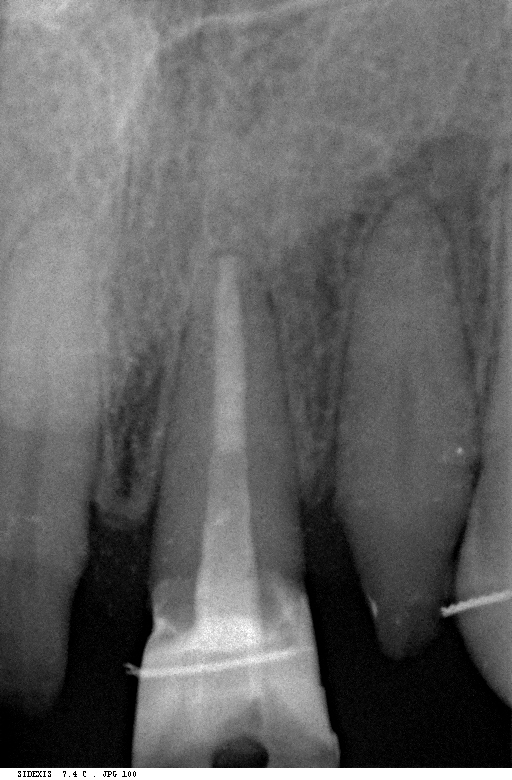

Post Extrusionem Veröffentlicht 16. März 2012 am 512 × 780 in Erzeugung eines Ferruleeffektes durch Extrusion eines Frontzahnes postendodontisch